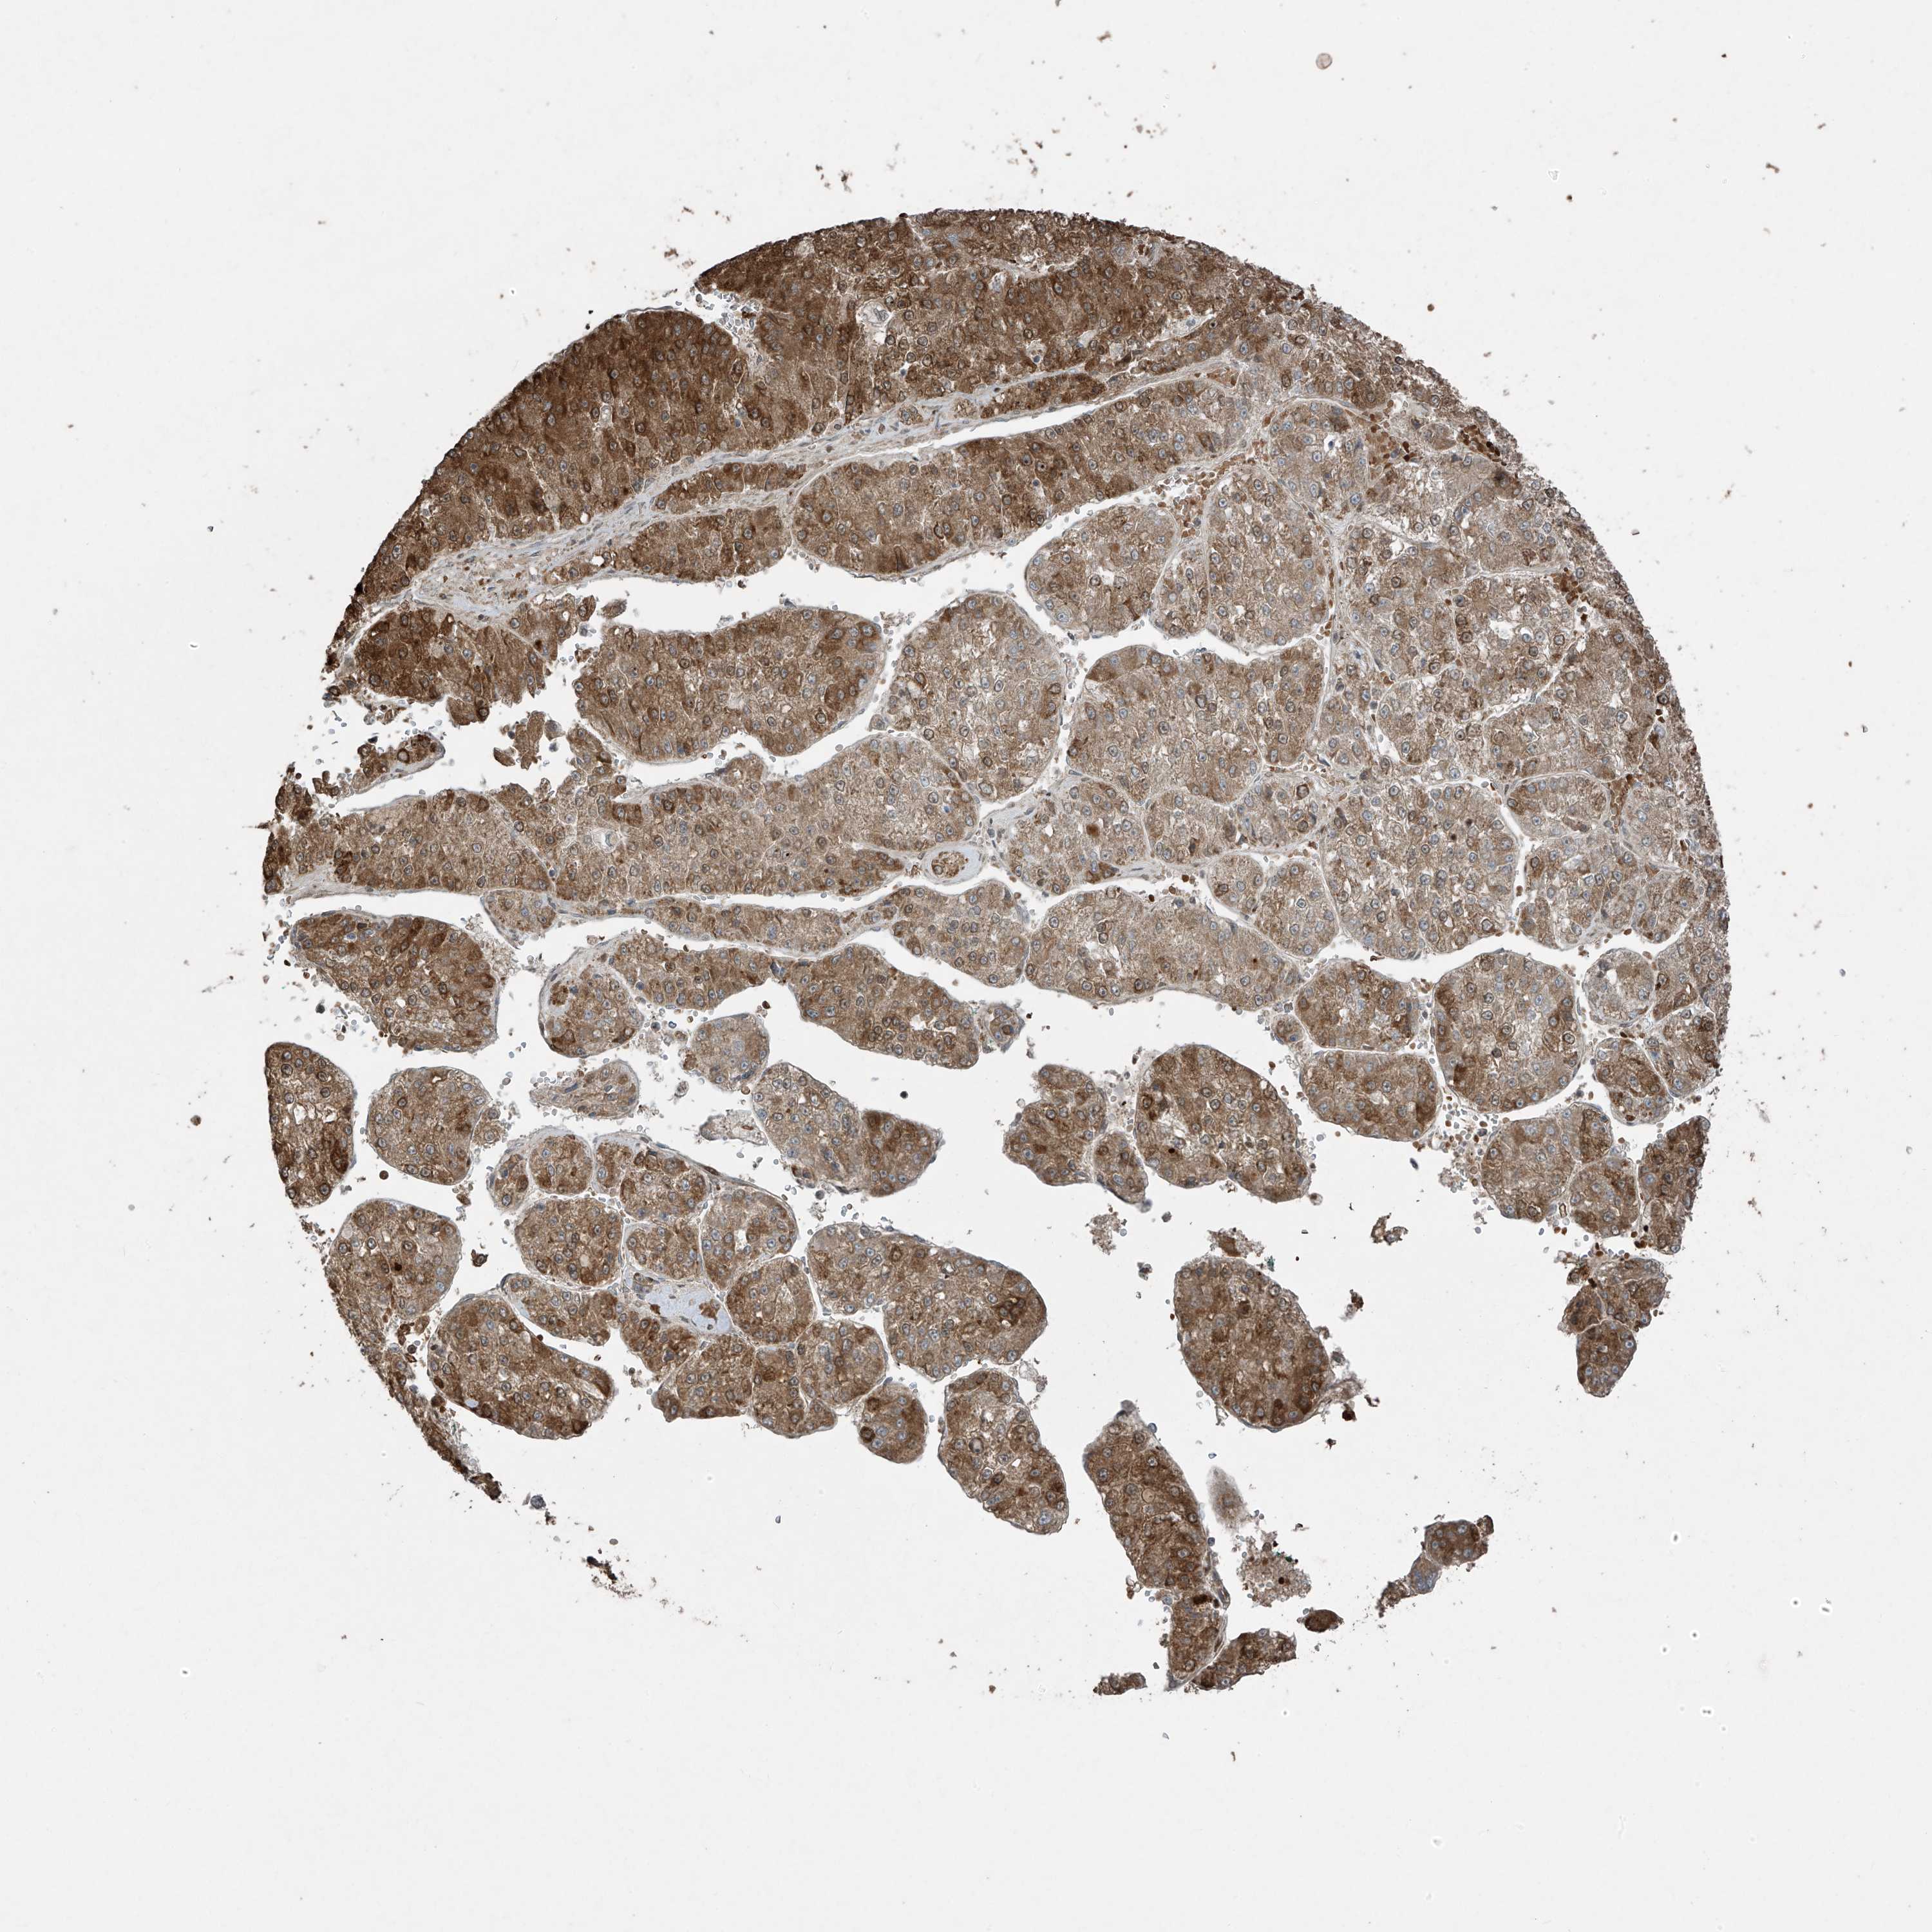

LIVER CANCER - Protein expressioni

A mouse-over function shows sample information and annotation data. Click on an image to view it in a full screen mode. Samples can be filtered based on level of antibody staining by selecting one or several of the following categories: high, medium, low and not detected. The assay and annotation is described here.

Note that samples used for immunohistochemistry by the Human Protein Atlas do not correspond to samples in the TCGA dataset.

Antibody stainingi

Antibody staining in the annotated cell types in the current human tissue is reported as not detected, low, medium, or high, based on conventional immunohistochemistry profiling in selected tissues. This score is based on the combination of the staining intensity and fraction of stained cells.

Each image is clickable and will lead to virtual microscopy that enables deeper exploration of all samples and also displays staining intensity scores, fraction scores and subcellular localization as well as patient and tissue information for each sample.

Antibody HPA035072

Staining

High

Medium

Low

Not detected

Intensity

Strong

Moderate

Weak

Negative

Quantity

>75%

75%-25%

<25%

None

Location

Nuclear

Cytoplasmic/membranous

Cytoplasmic/membranous,nuclear

Cholangiocarcinoma

Carcinoma, Hepatocellular, NOS